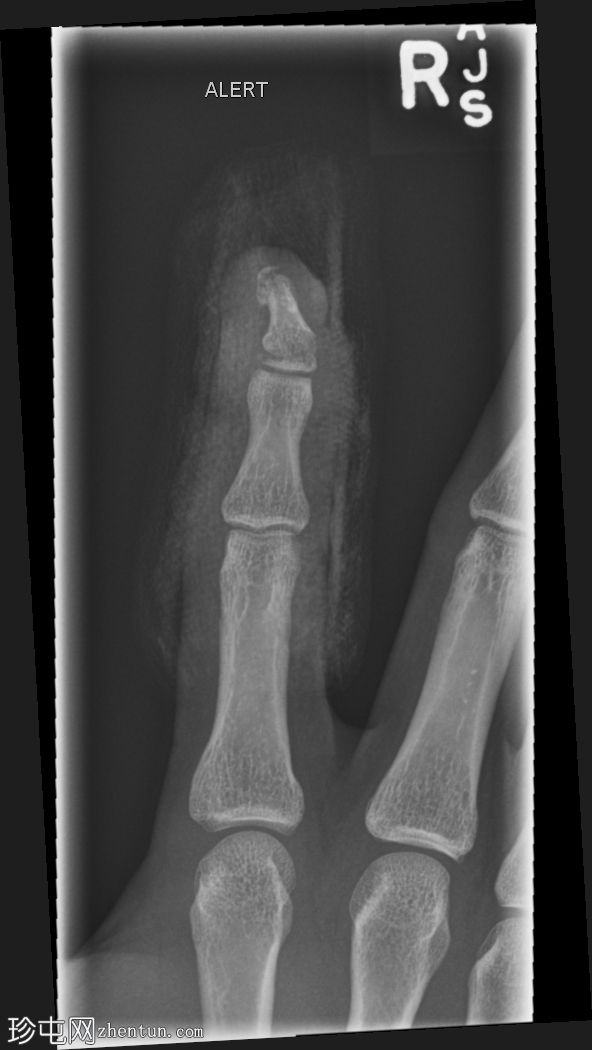

斜位片

右食指远节指骨基底部横向移位骨折,伴有背侧成角,最符合成人型Seymour骨折。指尖小骨折。

本例为罕见的成人型Seymour骨折,此类骨折通常发生于骨骼未成熟的远节指骨骨骺处。